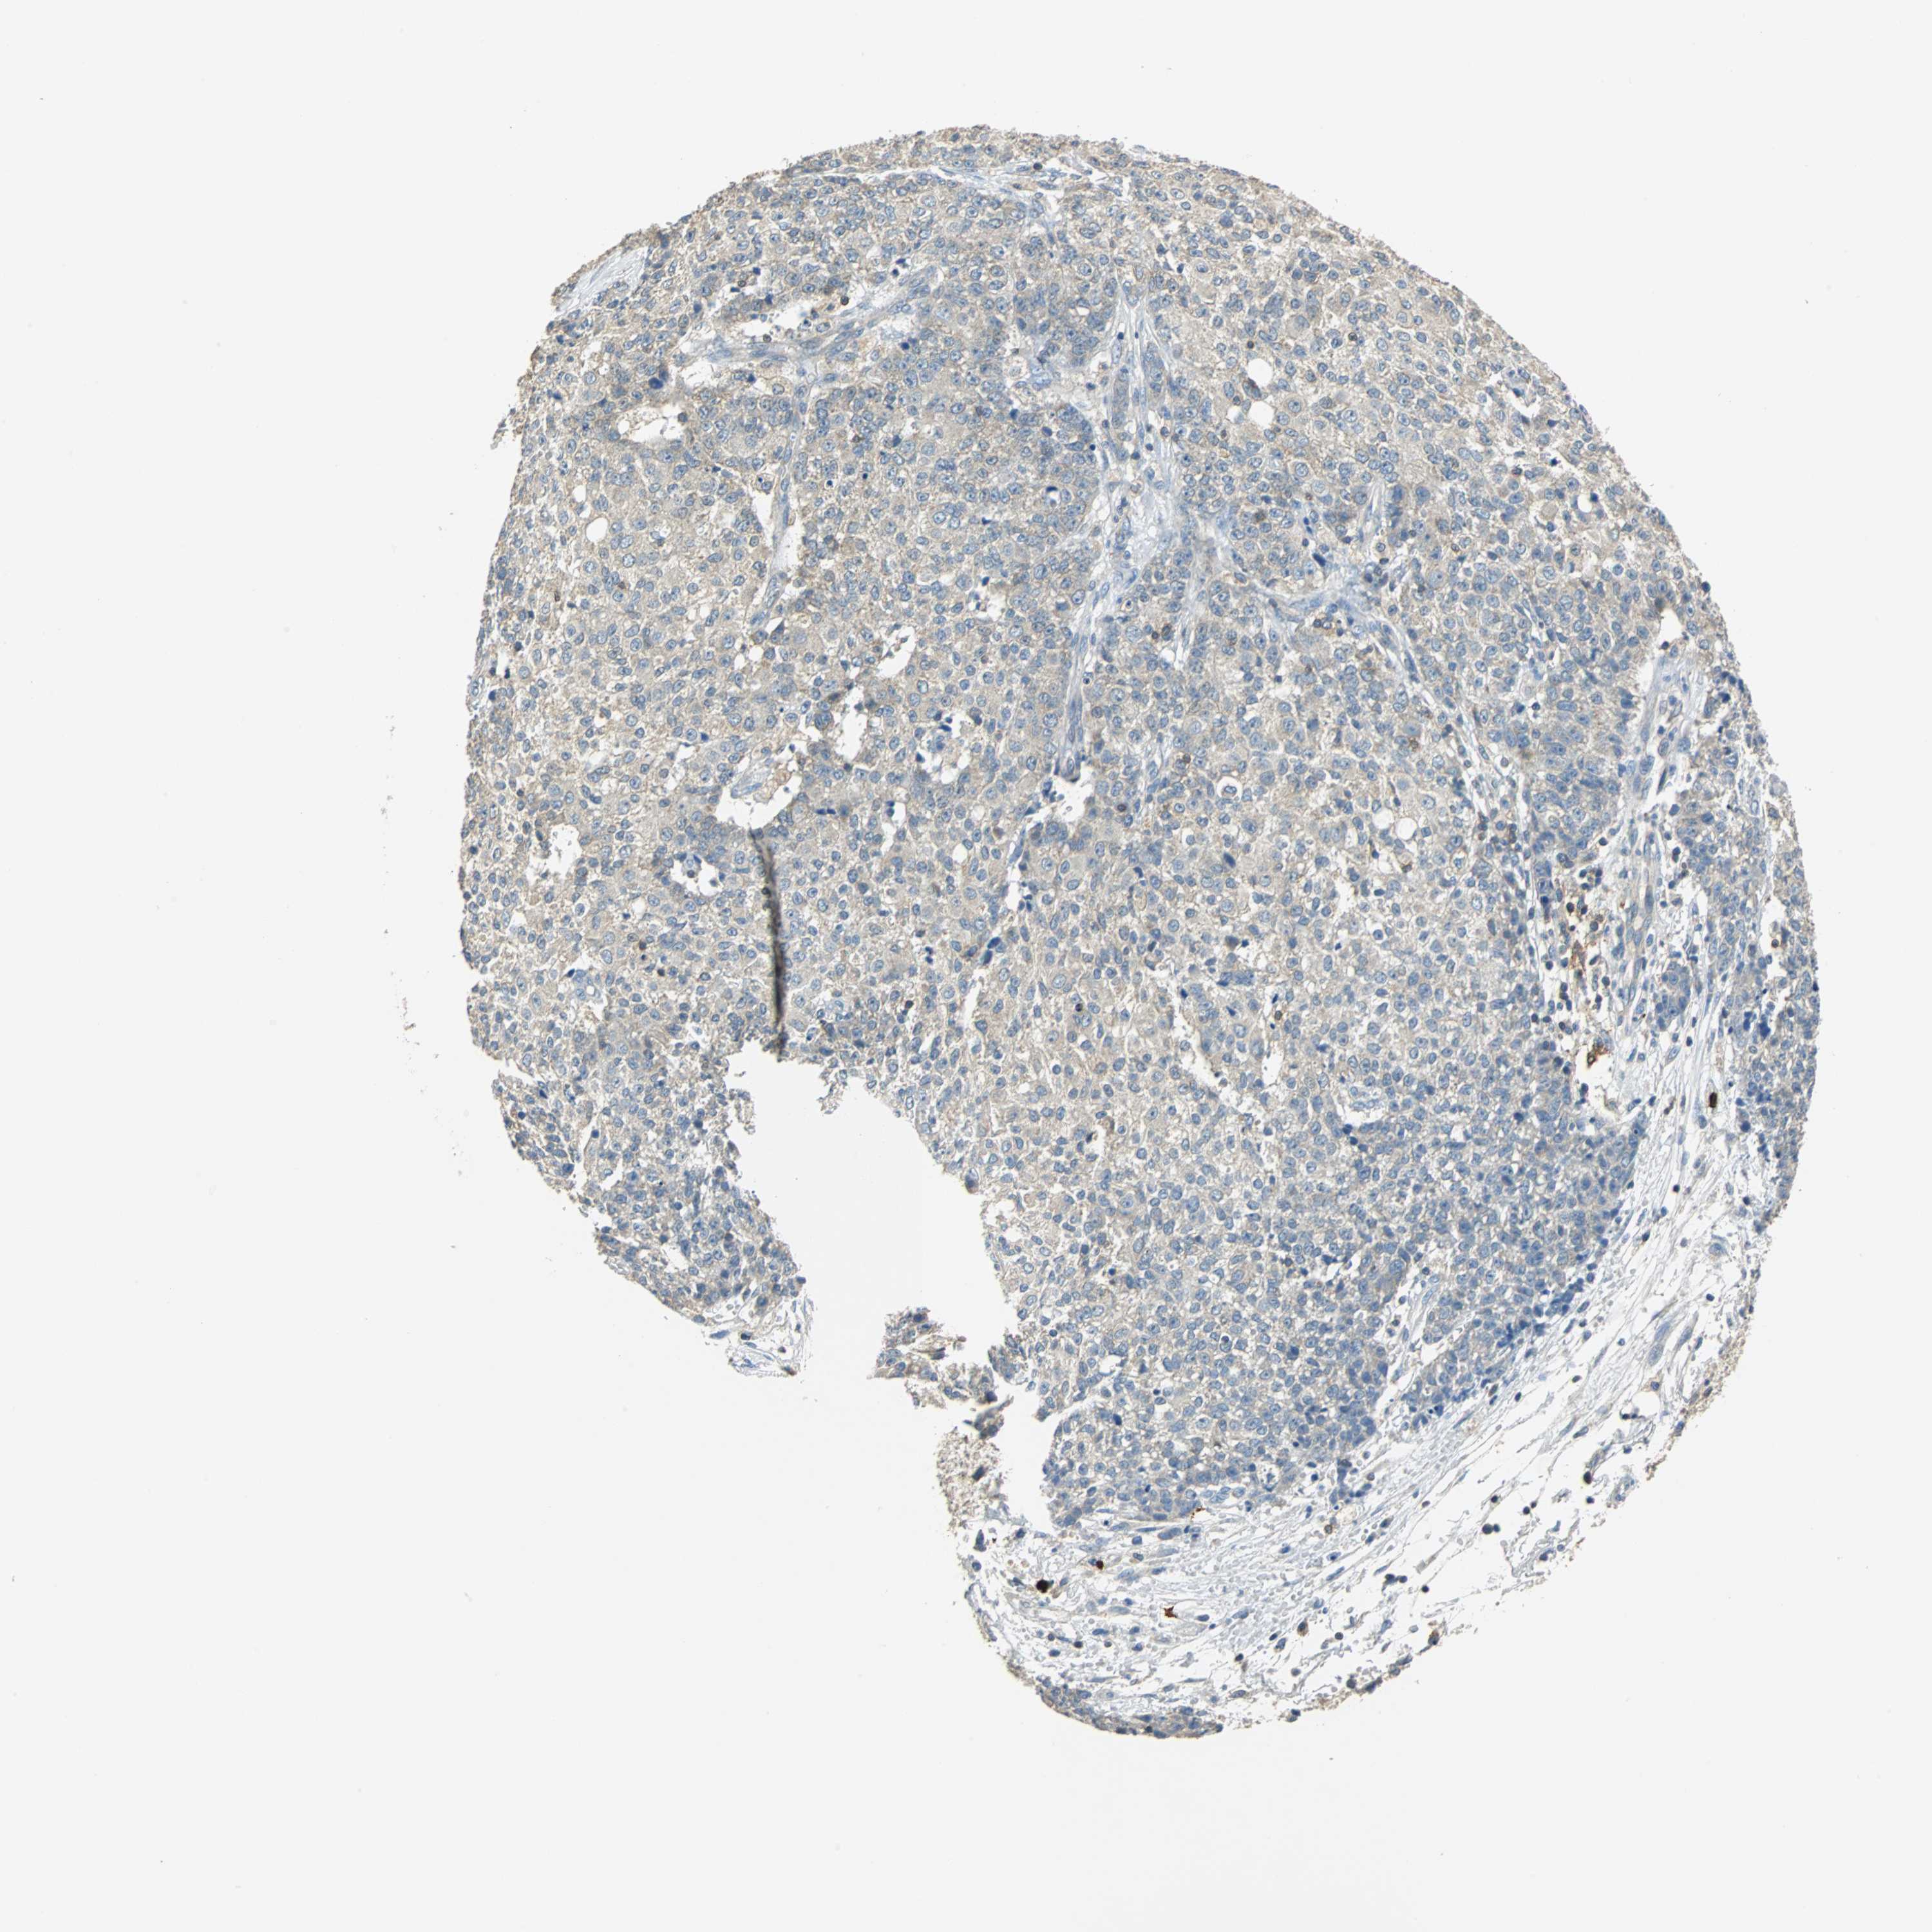

OVARIAN CANCER - Protein expressioni

A mouse-over function shows sample information and annotation data. Click on an image to view it in a full screen mode. Samples can be filtered based on level of antibody staining by selecting one or several of the following categories: high, medium, low and not detected. The assay and annotation is described here.

Note that samples used for immunohistochemistry by the Human Protein Atlas do not correspond to samples in the TCGA dataset.

Antibody stainingi

Antibody staining in the annotated cell types in the current human tissue is reported as not detected, low, medium, or high, based on conventional immunohistochemistry profiling in selected tissues. This score is based on the combination of the staining intensity and fraction of stained cells.

Each image is clickable and will lead to virtual microscopy that enables deeper exploration of all samples and also displays staining intensity scores, fraction scores and subcellular localization as well as patient and tissue information for each sample.

Antibody HPA006479

Antibody HPA008689

Antibody CAB020712

Cystadenocarcinoma, serous, NOS

Carcinoma, endometroid

Carcinoma, NOS

Cystadenocarcinoma, mucinous, NOS